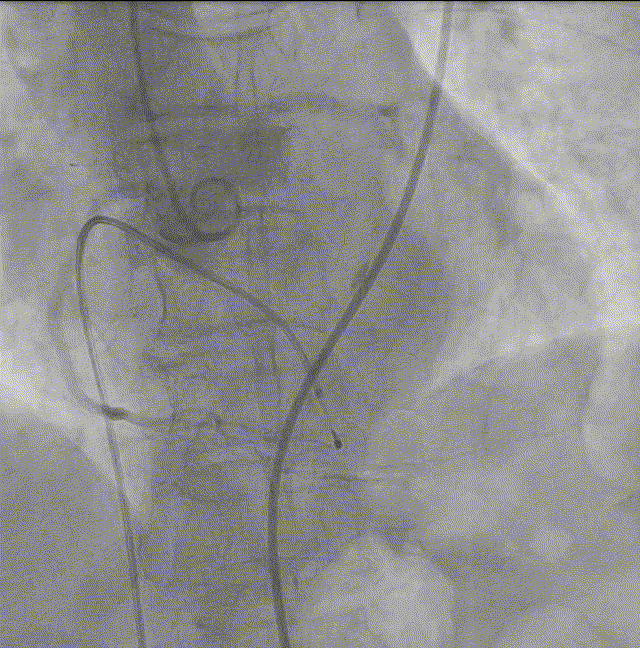

6. 20mm球囊预扩张;

球囊预扩张

6. 22mm球囊预扩张;